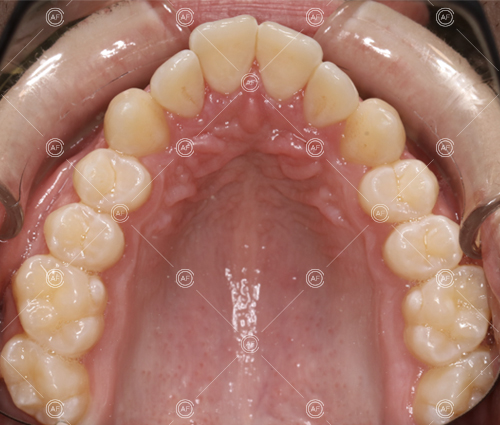

MH debonded in December 2020, with overall treatment time of around 14 months.

She was provided with upper and lower vacuum form retainers, and asked to wear these every night for the first year, and alternate nights for the second year onwards, indefinitely for as long as she wanted her teeth to remain straight. High quality finish was maintained at one year post-debond.